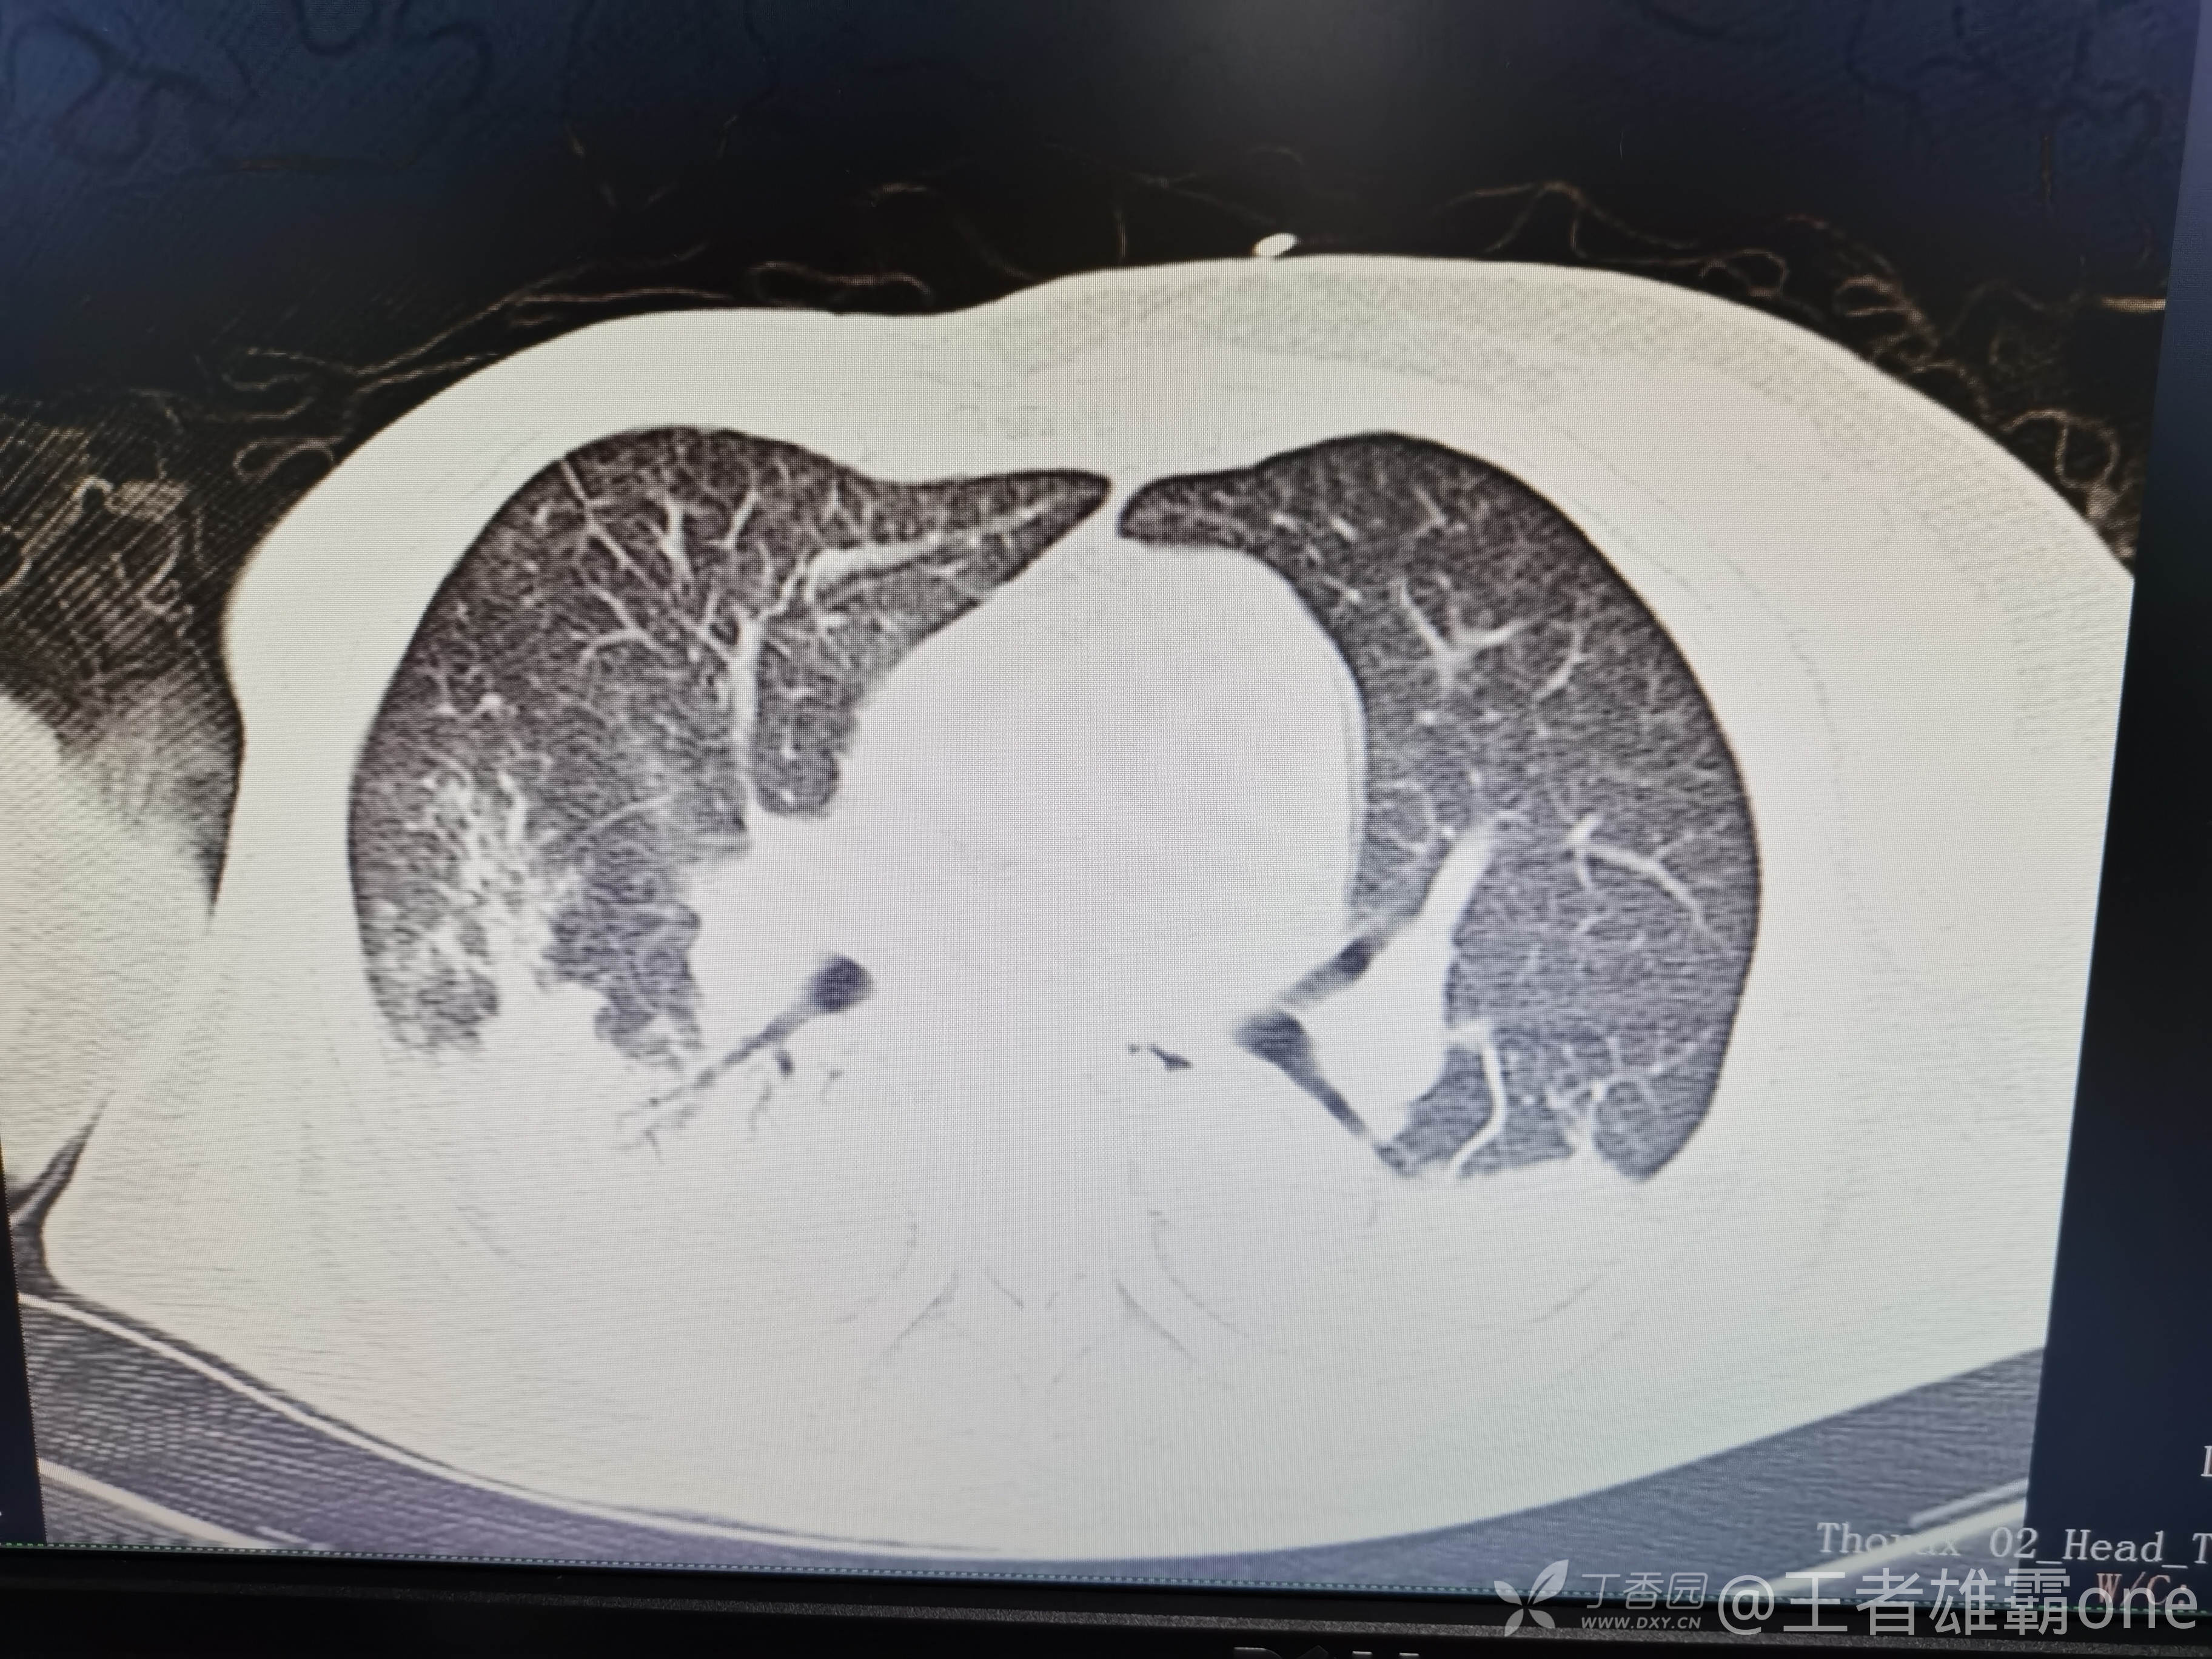

西门开心 推荐63岁女性,因车祸致短暂神志不清、多处疼痛4h入院。简单病史:伤后送至医院急诊就诊。完善头胸腹CT等检查,完善新冠核酸、血常规等化验。血常规提示血红蛋白62g/L。头颅CT提示未见明显外伤性改变。胸腹部CT视频见下:

5.肺挫伤

6.双侧多发肋骨骨折

12.双侧胸腔少量积液

早上复查血常规:血红蛋白100g/L,白细胞11.1×109/L,血小板29×109/L。凝血功能:APTT37.9s,纤维蛋白原3.01g/L,凝血酶时间18.6s,D二聚体21530ug/L。生化:白蛋白36.2g/L,胆红素指标正常,谷丙56U/L,总胆红素38mmol/L,直接胆红素12.1mmol/L,谷草57U/L,肌酐91.1ummol/L,尿素13.97mmol/L,超敏C反应蛋白142.1mg/L。降钙素原17.70ng/ml。脑钠肽前体2164pg/ml。复查胸部CT: